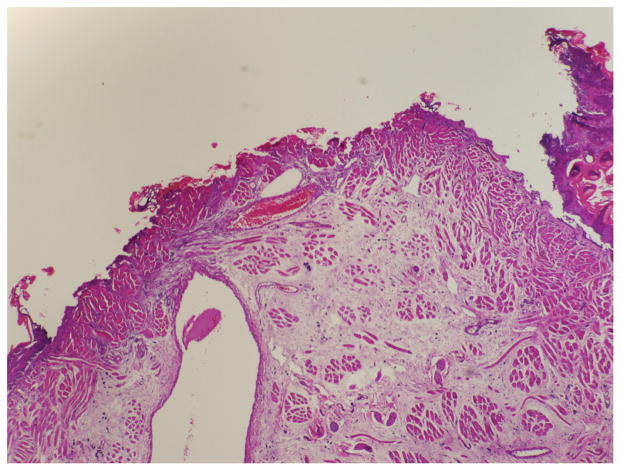

Histology

Mucosal wound-healing scale scores were recorded for each rat and averaged among the surgical groups. Photographs were taken of the histologic sections (Figures 4 and 5).

Figure 4.

Hematoxylin and eosin stain showing a high mucosal wound-healing scale (significant surface crusting, vessel wall necrosis, epithelium, neutrophils, and myofibroblasts).